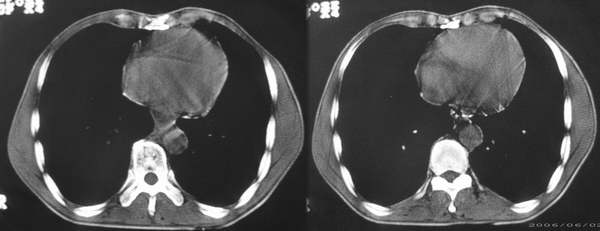

患者,男,58岁。吞咽困难3个月,胃镜示食管中、下段狭窄,右后壁隆起,黏膜表面光滑柔软无破坏。正常图象未上传

食管中下段右后壁明显增厚,管腔狭窄,考虑食管癌,做一下食道吞钡应该可以更进一步证实。

中下段管壁明显增厚,不均匀,且可见有向腔内突入的软组织,考虑食道癌.

常规考虑食道癌,但是,胃镜未发现具体病变(粘膜完整,柔软),应此,钡餐检查只能考虑为食道外压性改变,所以,增强显得较重要,建议增强ct检查,就该图片,不排除食道平滑肌瘤可能。

食管中下段右后壁软组织肿块,管腔变窄,隆突下见肿大淋巴结。考虑食管癌淋巴结转移。

结合胃镜检查,食管中下段右后壁软组织肿块,考虑食道平滑肌瘤可能。建议增强和钡透。

胃镜示食管中、下段狭窄,右后壁隆起,黏膜表面光滑柔软无破坏。\"提示并非食管粘膜的病变。而食管癌是起至于粘膜层。上述ct图像提示:食管壁较均匀地增厚,故首先考虑食管肌层的病变,平滑肌瘤、纤维瘤、神经纤维瘤、血管瘤等良性病变常为食管偏侧性肿块,食管壁局限性增厚,所以该病例应为来自食管肌层的病变的恶性病变,平滑肌肉瘤的可能性大,类癌不除外。